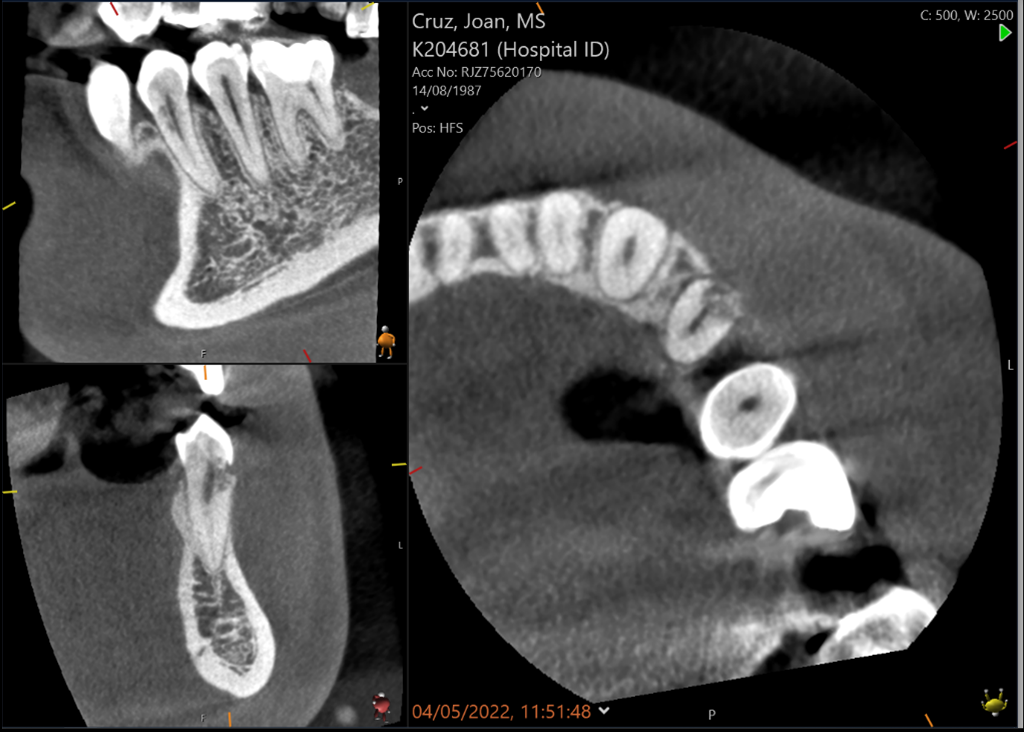

UL6 Internal inflammatory resorption perforating palatal root. Repaired with MTA.

12 month review (crown carried out by GDP)